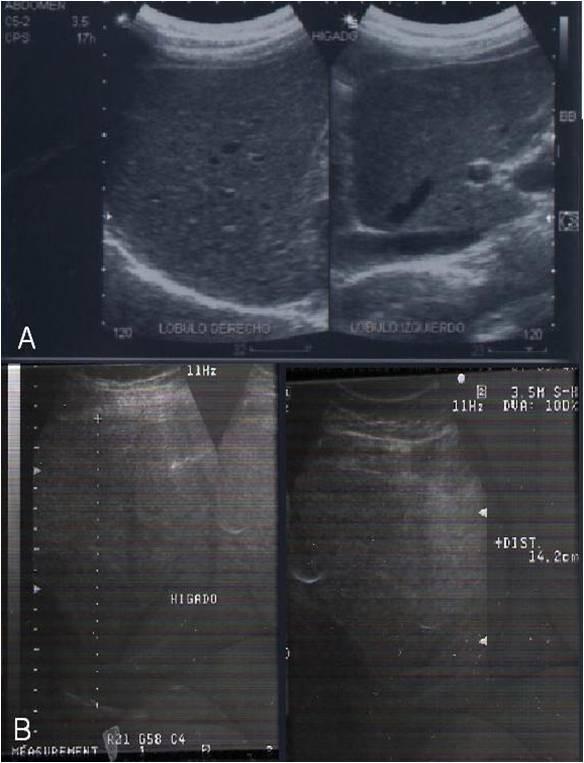

Three Hispanic Mexican patients (a 43-year-old man, a 77-year-old man and a 44-year-old woman) underwent ultrasonography and were treated with 4.5 g/day of Spirulina maxima for three months. Their blood samples before and after the treatment determined triacylglycerols, total cholesterol, high-density lipoprotein cholesterol, alanine aminotransferase and low-density lipoprotein cholesterol levels. The results were assessed using ultrasound.

Treatment had therapeutic effects as evidenced by ultrasonography and the aminotransferase data. Hypolipidemic effects were also shown. We conclude that Spirulina maxima may be considered an alternative treatment for patients with non-alcoholic fatty liver diseases and dyslipidemic disorder.